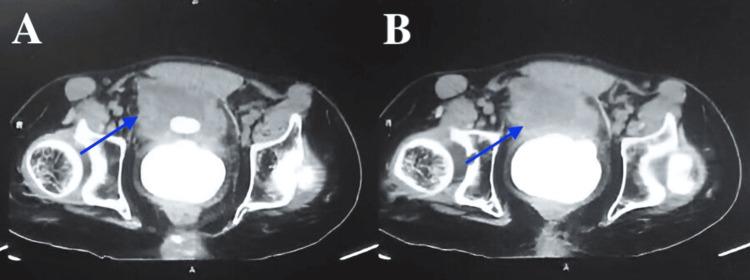

Prostate calculi, or prostatic stones, are typically small, greyish-brown, ultrasound-dense formations composed mainly of carbonated calcium phosphate apatite. We present a 65-year-old male with severe lower urinary tract symptoms (LUTS), including weak urinary stream, difficulty urinating, and acute retention, who was found to have a 4 cm prostate stone. Imaging confirmed obstruction of the prostatic urethra. Surgical intervention with transurethral resection of the prostate (TURP) and Holmium laser lithotripsy successfully removed the stone and relieved symptoms. This case emphasizes the need to consider prostate stones in severe LUTS when conventional treatments fail, with regular follow-up to monitor recurrence.

前列腺结石,又称前列腺石,通常体积较小,呈灰棕色,超声检查显示为密度较高的结构,主要由碳酸磷酸钙磷灰石组成。我们报告一例65岁男性,患有严重的下尿路症状(LUTS),包括尿流无力、排尿困难和急性尿潴留,经检查发现有一枚4厘米的前列腺结石。影像学检查证实前列腺尿道梗阻。经尿道前列腺切除术(TURP)和钬激光碎石术的手术干预成功取出结石并缓解了症状。该病例强调,当常规治疗无效时,对于严重的LUTS需要考虑前列腺结石的可能,并进行定期随访以监测复发情况。